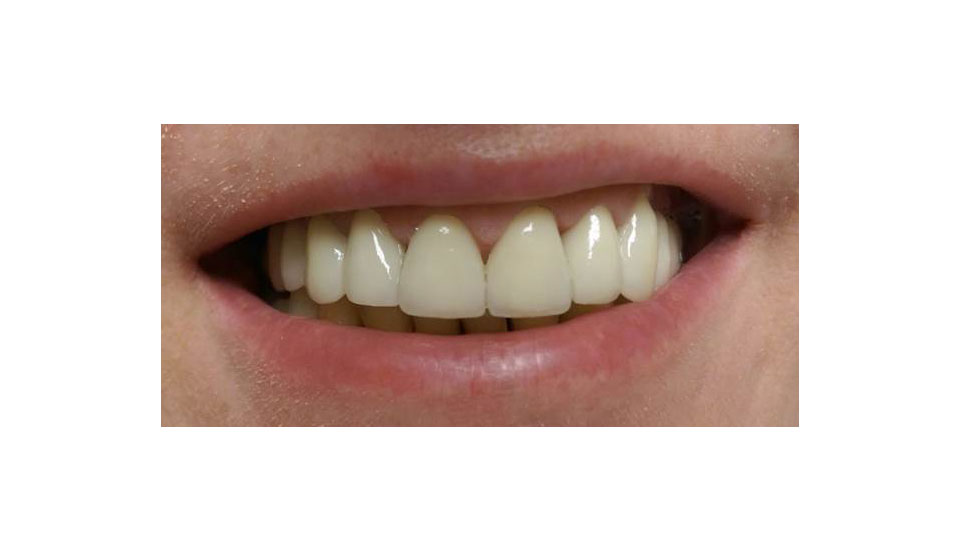

Elhanyagolt fogsor cseréje 2 nap alatt

2 nap alatt varázsoltuk ezt a szép esztétikus alsó, felső körhídat implantátumokkal megtámasztva a korábban elhanyagolt szájba. Az 1. nap 26 fogat távolítottunk el, mert annyira rossz állapotban voltak, és rögtön azonnal terhelhető IHDE svájci implantátumokat raktunk be, fentre 8, lentre 6 darabot. A sebeket összevarrtuk és intraorális szkennerrel digitális lenyomatot vettünk. 2 nap múlva pedig beragasztottuk a kész PMMA műanyag körhidakat. Dr. Kelemen Péter és a Symbion Fogtechnika munkája.